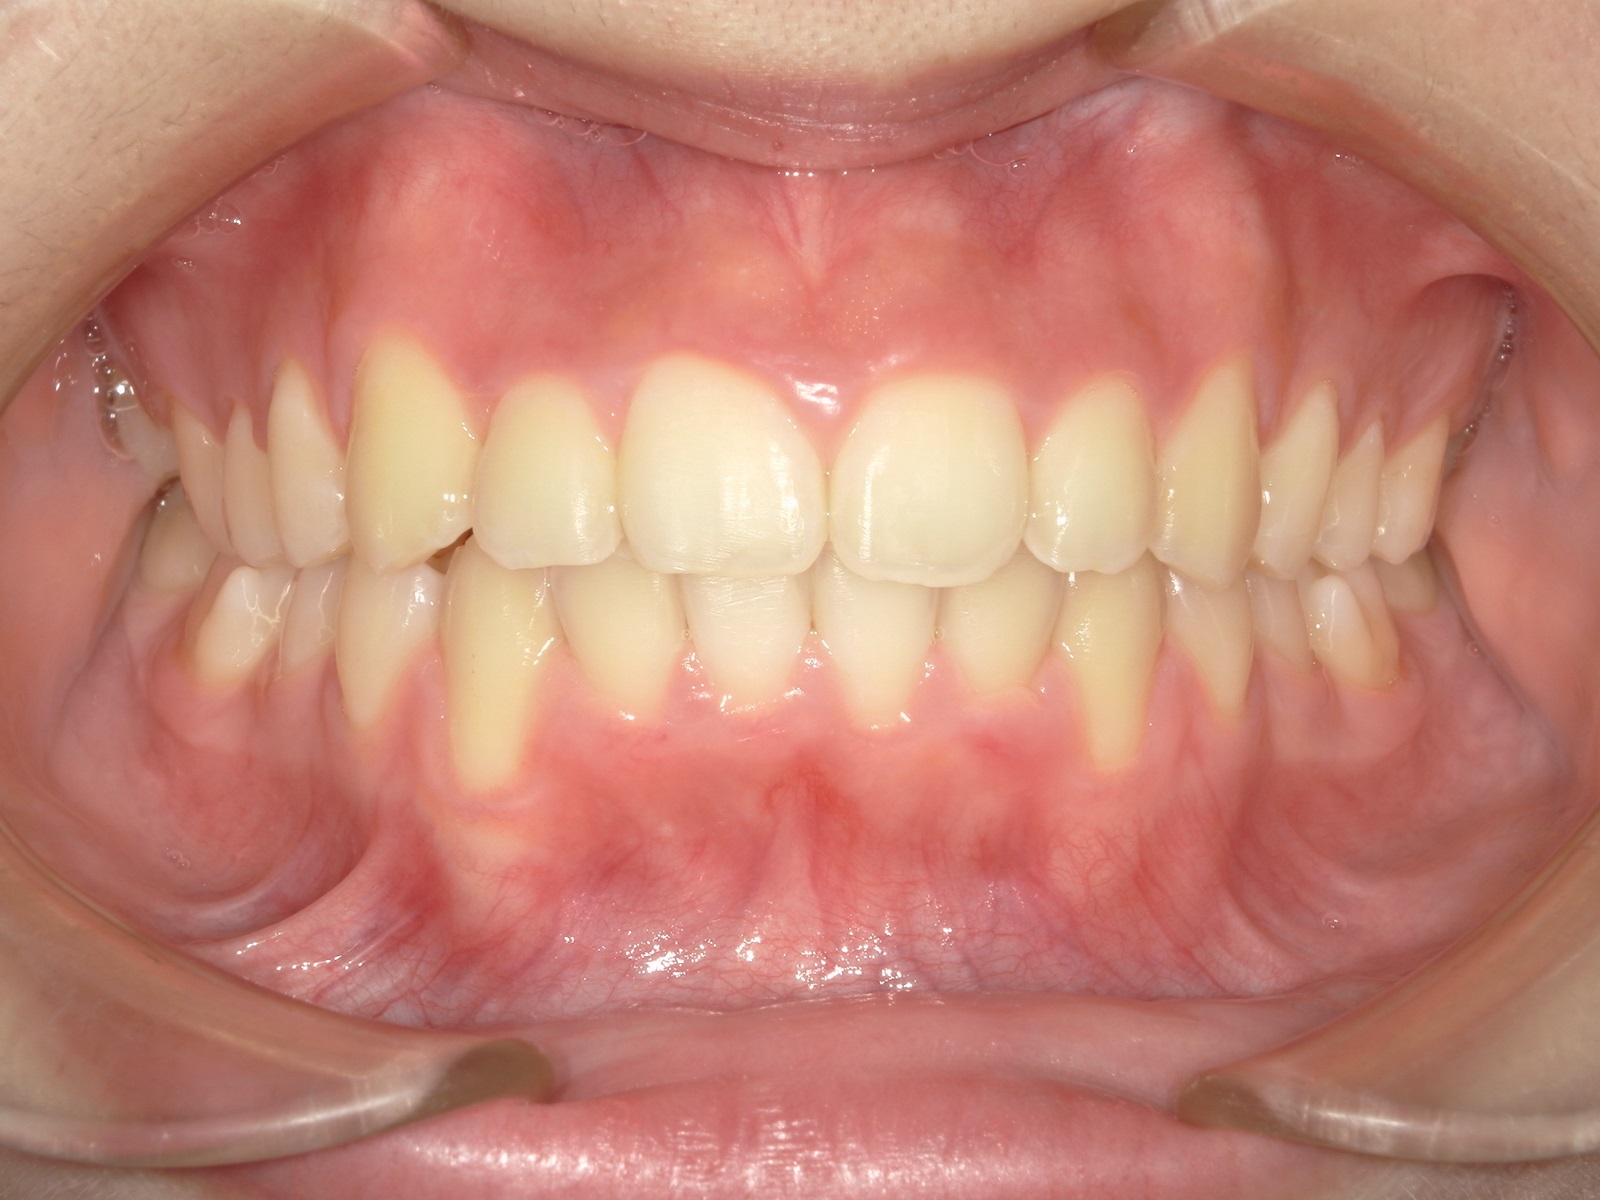

歯がデコボコに並んだ歯並びのことを「叢生(そうせい)」と言います。「乱ぐい歯」という名前でも知られています。叢生の歯並びの中で、よく知られているのが、上顎の犬歯が前方に突出している「八重歯」です。八重歯は可愛らしいイメージに捉えられることもありますが、歯並びとしては良くない、デコボコ歯並びの一種です。

当院では、以下の2つの矯正治療法と矯正装置を取り揃えており、患者さん一人ひとりの歯並びやご希望に応じて、最適な治療法をご提案いたします。